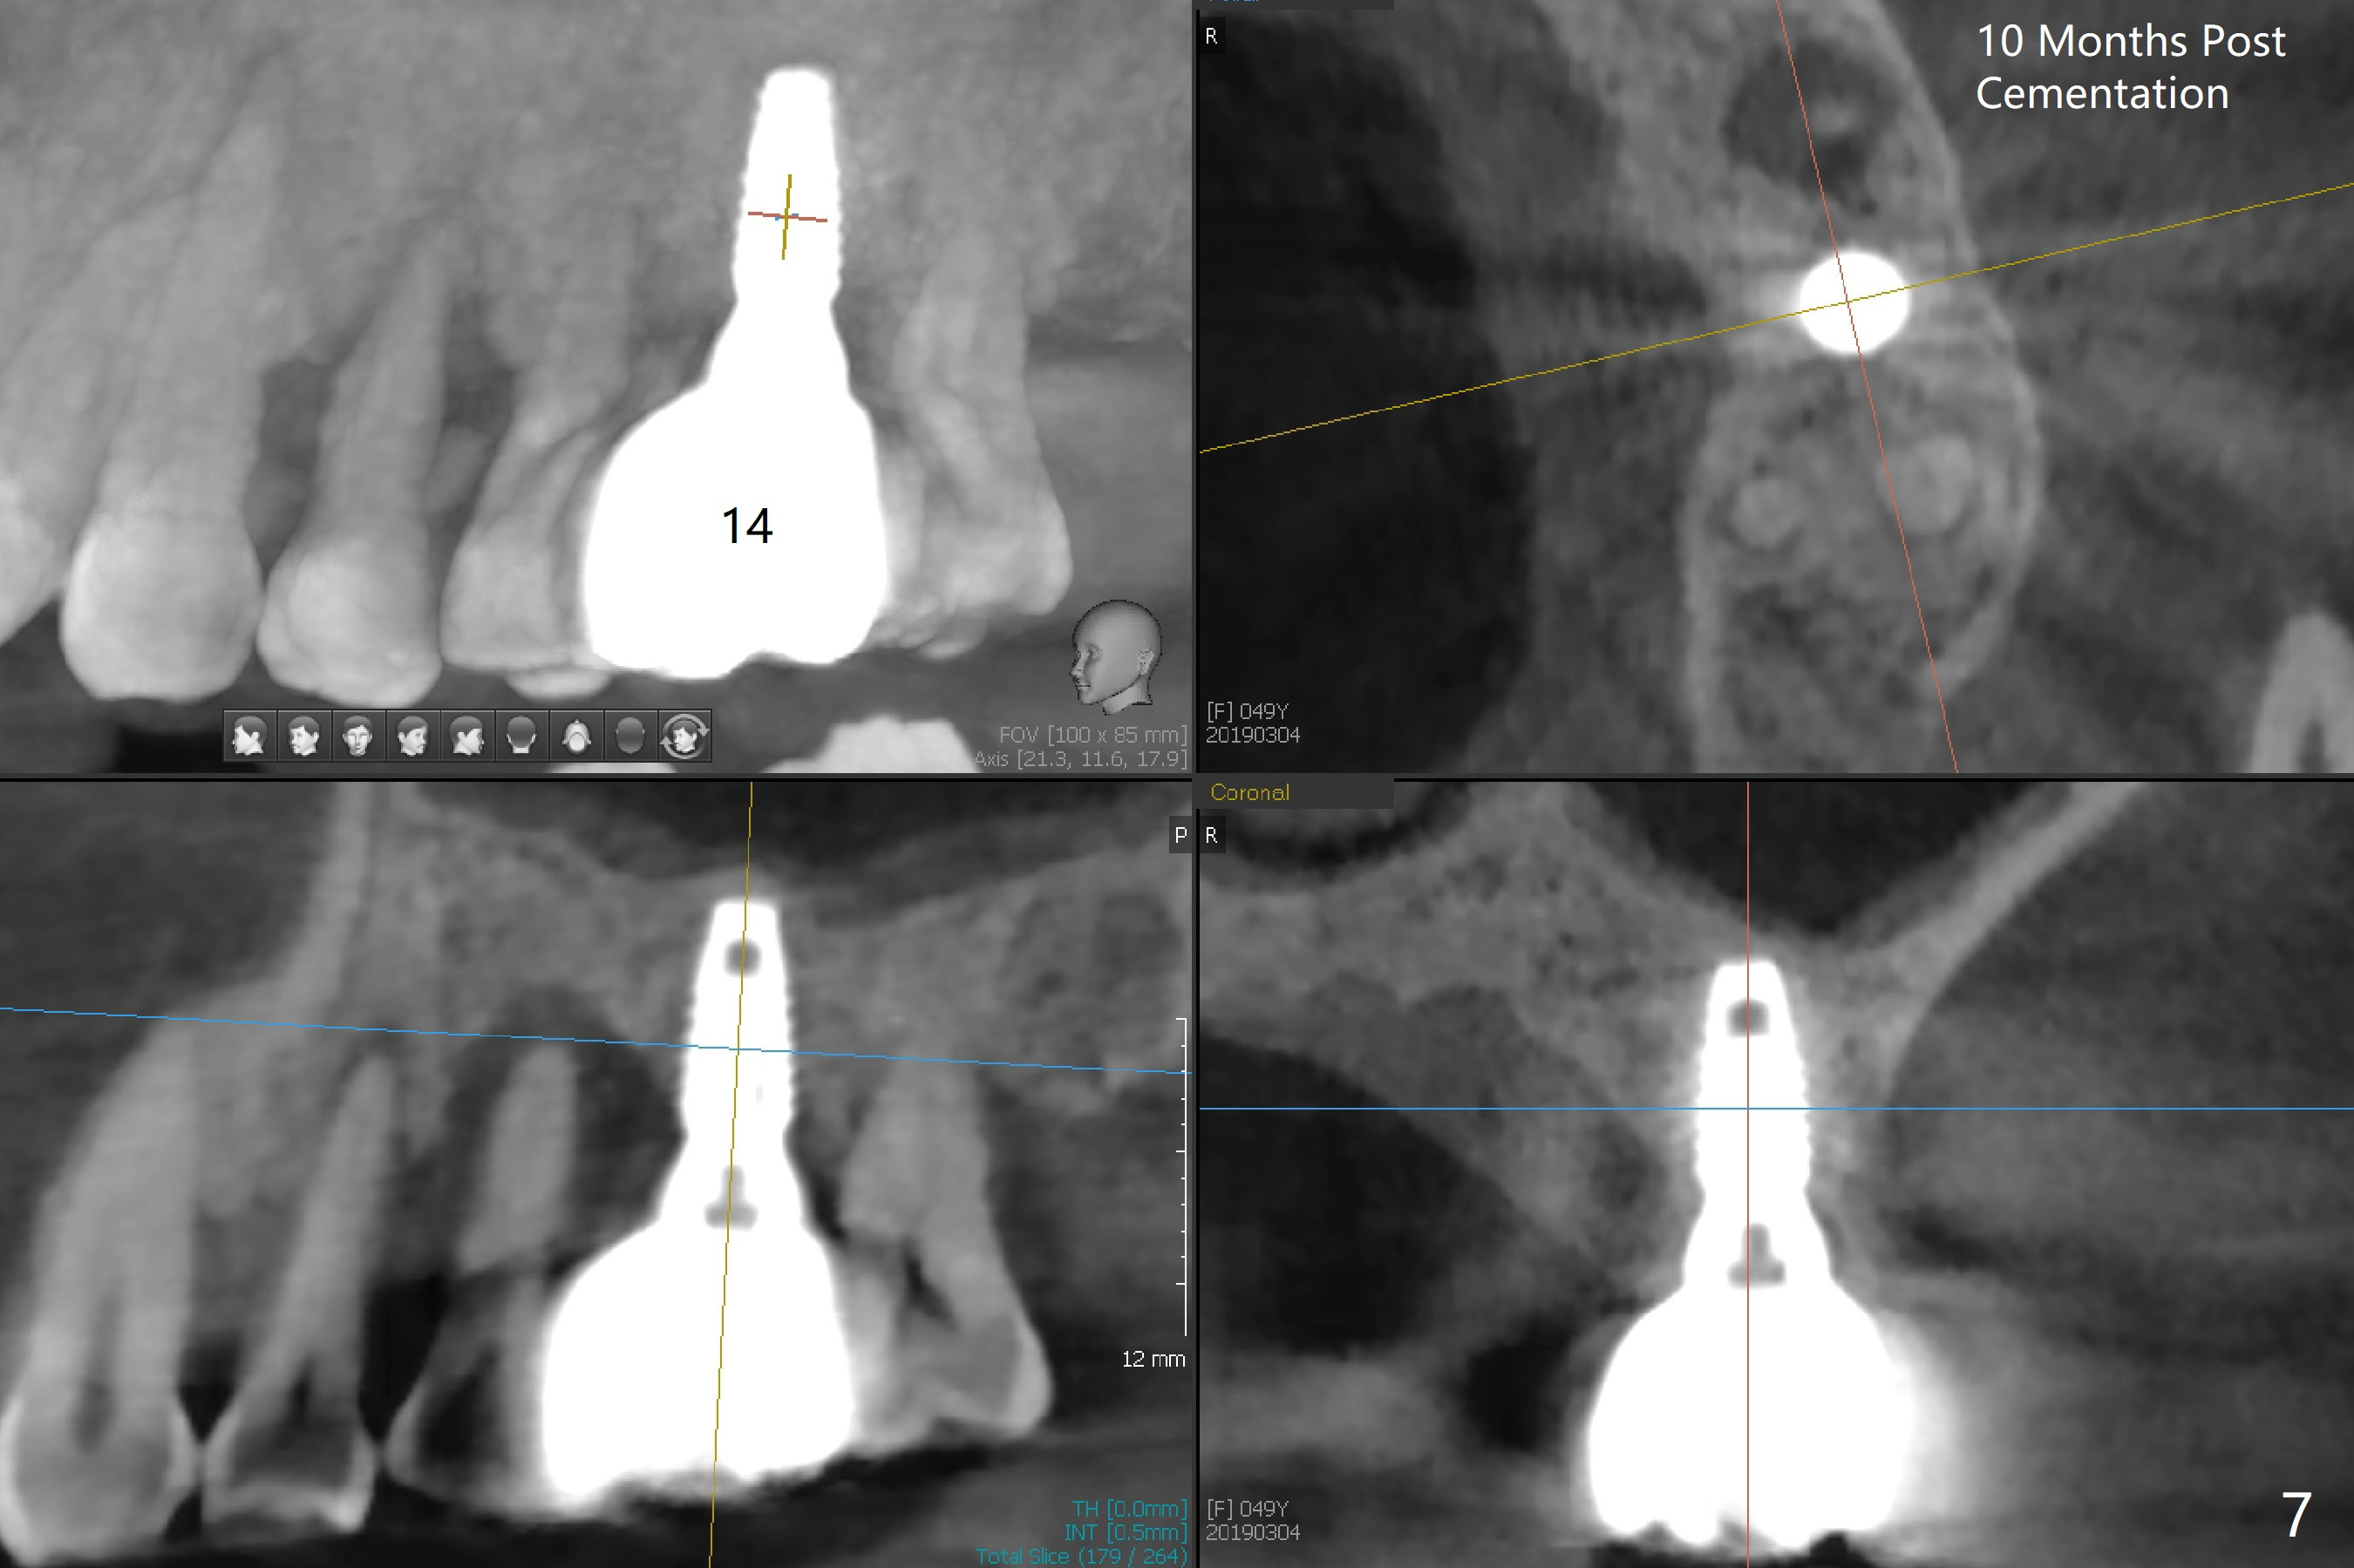

Bone height at #14 two months post exfoliation is ~ 4 mm (Fig.1). Bone expansion is difficult because of dense bone. After drilling, a 4.5 mm tap is inserted with stability (Fig.2). Sinus lift is accomplished with RT3 and autogenous bone prior to placement of a 4.5x8.5 mm implant (Fig.3). Because of flapless surgery and tight and long gingiva, bone graft around the coronal end of the implant is intentionally not placed. A 5.5x5(4) mm abutment is immediately placed for an immediate provisional. (Fig.4). Take PA and impression when the patient returns. The provisional dislodges 3.5 months postop (Fig.4); impression is taken. The patient reports hot sensitivity and pain after meal at the implant site (Fig.5). After removal of the implant crown/abutment, she feels better. If not, it seems necessary to extract the tooth #13 for a 13 mm long implant with a mill abutment (Fig.6).